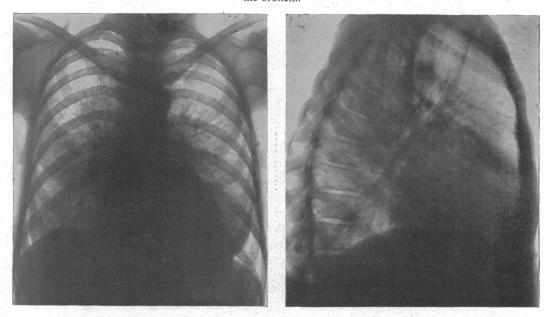

The radiology of acute pulmonary oedema.

Br Heart J. 1951 Oct;13(4):503-18. doi: 10.1136/hrt.13.4.503.